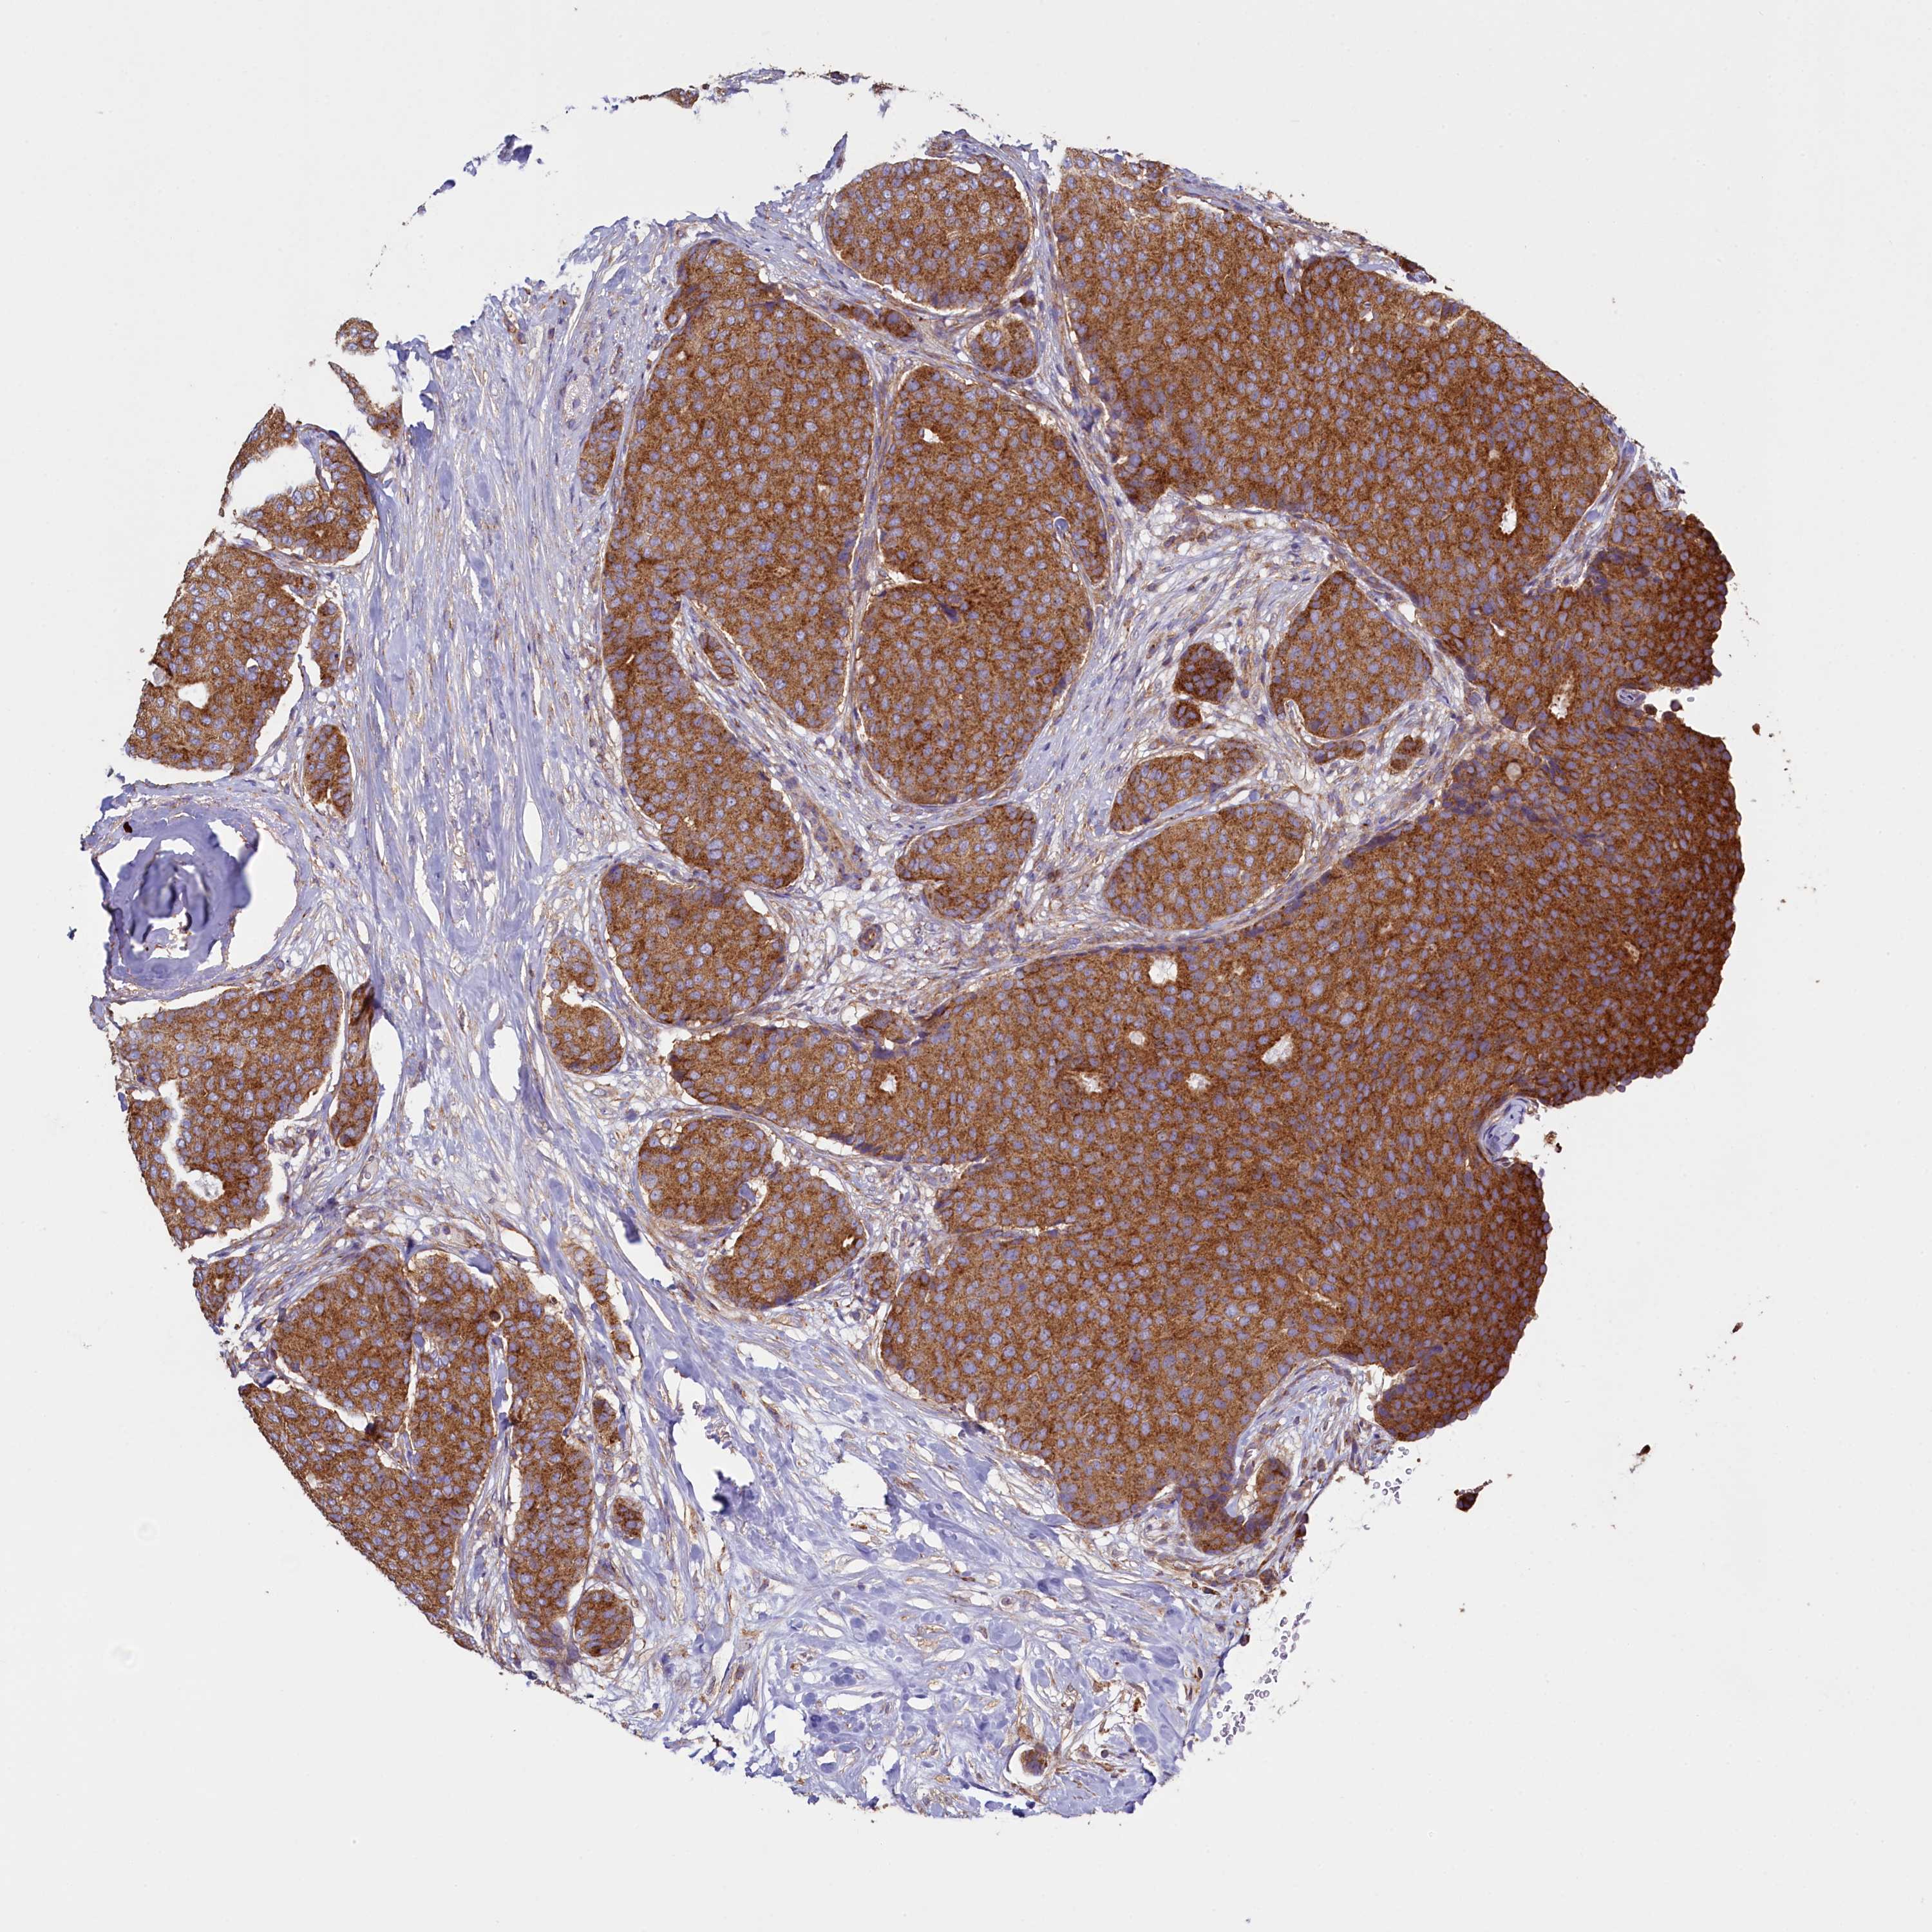

CANCER BREAST CANCER Show tissue menu

BRCA TCGA BRCA VALIDATION PROTEIN EXPRESSION